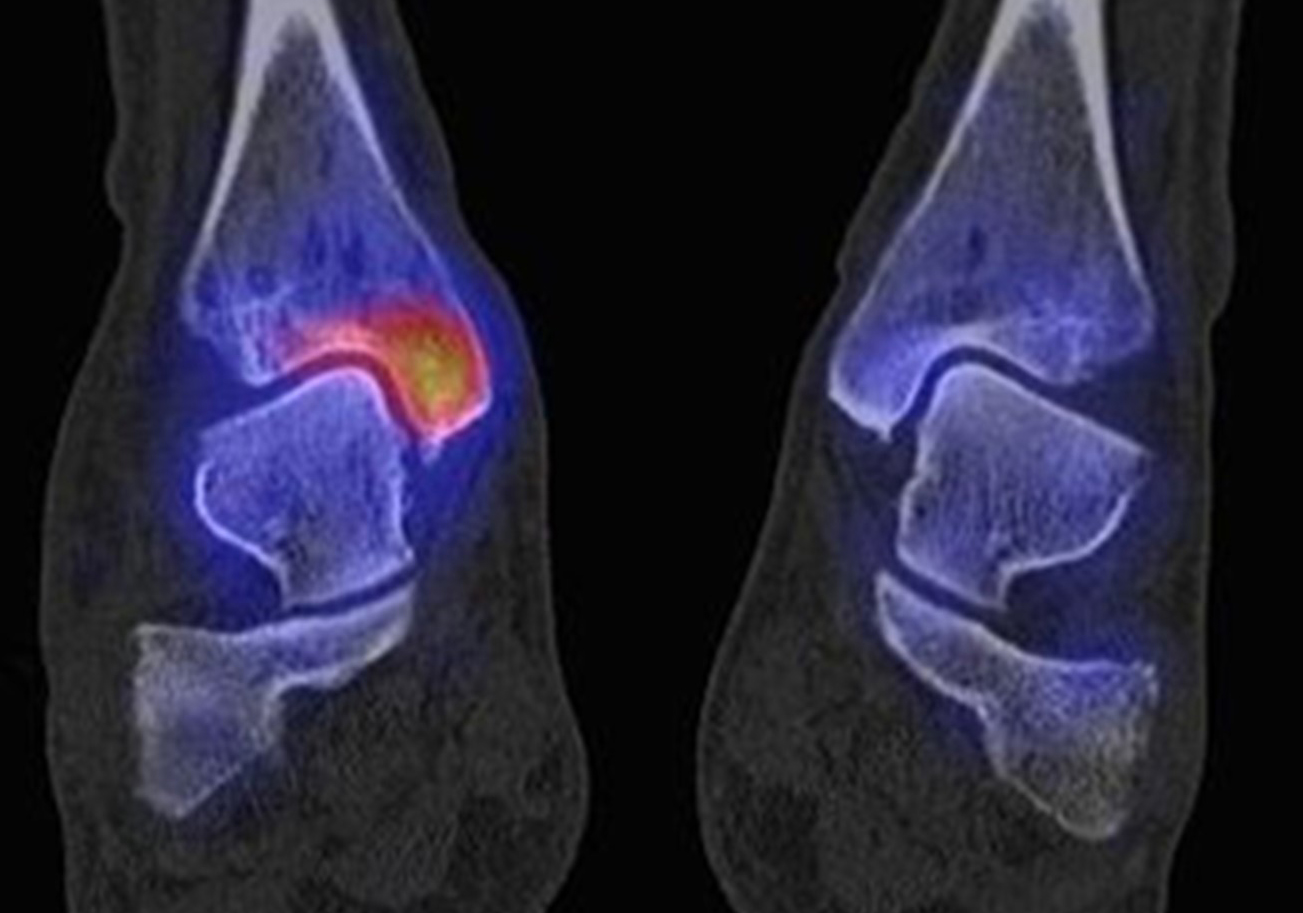

Osteonekrosen

Abbildung 9.2.a bis d: SPECT/CT zur Beurteilung der Knochen-Vitalität bei einer Talusnekrose. 5 Jahre zuvor während der Arbeit war die Patientin beim Treppensteigen umgeknickt und zog sich Außenbandrupturen zu. Nachfolgend persistierende Beschwerden mit Entwicklung einer Talusnekrose. Frage nach Vitalität und Ausdehnung der Nekrose. Deutliche bis intensive Traceranreicherung im Bereich des linken Talus. Im SPECT/CT befindet sich der Hypermetabolismus in allen Abschnitten des Talus mit relativer Aussparung eines sich demarkierenden Fragmentes lateral, was die laterale Talusschulter umfasst, die Größe beträgt transversal ca. 23 x 16 mm. In diesem Fragment relativ homogene Skelettstruktur, diese Befunde weisen auf eine trophische bzw. nekrotische Störung des Talus hin mit einem sich demarkierendem Fragment, welches die laterale Talusschulter beinhaltet.

Die Abbildung 9.3.a bis d zeigt ein weiteren Fall mit einer SPECT/CT zur Beurteilung der Knochen-Vitalität bei einer Talusnekrose. Die Bilder zeigen eine abgelaufene Nekrose mit zystischen Resorptionen des linken Talusdoms bei nachweislich erhaltener Vitalität der umgebenden Knochenabschnitte aufgrund des hier überall deutlich erhöhten Knochenmetabolismus (= inkomplette Restitutio). Aufgrund der nachweislich erhaltenen Vitalität konnte erfolgreich eine Knochen-Transplantation erfolgen.Deutlich geringer ausgeprägte nekrotische Veränderungen auch im rechten Talusdom bei hier weitgehend erhaltenen Gelenkkonturen.